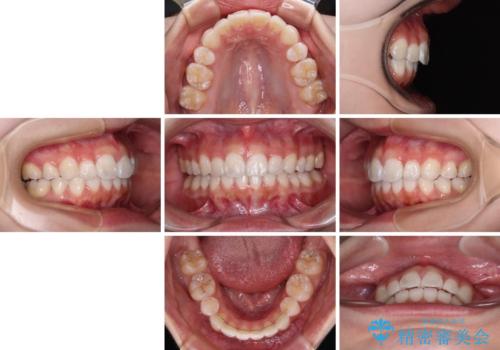

- 上下前歯の叢生を気にして来院された患者様です。

インビザラインでの治療を希望されていて、デコボコの程度が中等度であり、安価なパッケージにて対応可能と判断されたため、インビザライン・モデレートを用いて矯正治療を行うこととしました。

インビザライン・モデレートは、製作できるアライナーの枚数に制限があるため、移動可能な量に限りがあるものの、インビザライン・ライトよりも枚数が多いため、幅広い症例に対応可能です。